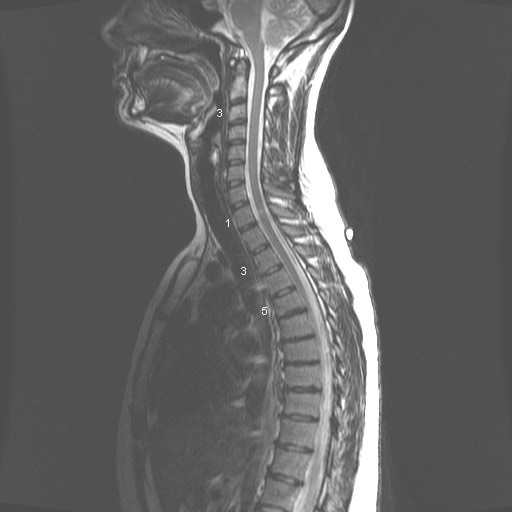

MRI

MRI 2

Hello and thank you for taking your time to read this and I apologize for the length of this. :) I am a 30 year old female and I have been having chronic back pain for quite a few years with the pain increasing in intensity steadily for the past 3 years. I used to figure skate competitively from age 10 to 17. While I did not sustain any major back injuries during that period, I think it would be safe to say my spine definitely did things it was never designed to do for long periods of time. I have seen a few doctors regarding this matter, one of which said something to the effect of "i don't see anything unusual here" regarding my MRI results while another's opinion was "you are too young to have these problems in your spine" and a nurse in the office of the MRI ordering Dr. who said "I don't know how you even move". I've tried to decipher the MRI reading myself but have trouble putting it all together.

The summary of my MRI as follows (age 27 at time of MRI):

THORACIC SPINE MRI WITHOUT IV CONTRAST, 9/24/2010 CLINICAL HISTORY: Chronic mid back pain. Multiple injuries. Bilateral lower extremity pain and numbness. COMPARISON: None. FINDINGS: There is a mild thoracic scoliosis that is convex right and centered at the T7-T8 level. The thoracic vertebral body heights and anterior-posterior alignment appear unremarkable, without evidence of compression fracture or spondylolisthesis. There are multilevel anterior marginal osteophyte formations most notably in the midthoracic spine between T6 and T9. There are mild multilevel facet joint degenerative changes in the thoracic spine. There is a small left lateral T5-T6 disc protrusion that results in mild central spinal canal stenosis. There are tiny right paracentral T6-T7 and T7-T8 disc protrusions. There is a tiny left paracentral T8-T9 disc protrusion. There is a small right lateral T11-T12 disc protrusion that results in mild right lateral recess stenosis. There is mild multilevel disc bulging in the thoracic spine. There is no significant neural foraminal stenosis in the thoracic spine. The thoracic spinal cord appears unremarkable in size and signal intensity, without evidence of cord compression or edema. The conus medullaris terminates at the L1 level and appears unremarkable in size and signal intensity.

IMPRESSION: Small left lateral T5-T6 disc protrusion, which results in mild central spinal canal stenosis. Tiny right paracentral T6-T7 and T7-T8 disc protrusions. Tiny left paracentral T8-T9 disc protrusion. Small right lateral T11-T12 disc protrusion, which results in mild right lateral recess stenosis. Mild multilevel disc bulging and facet joint degenerative changes in the thoracic spine. No significant neural foraminal stenosis in the thoracic spine.

FINDINGS: Examination of the alignment of the lumbar spine demonstrates it to be unremarkable. Bone marrow signal, spinal cord signal, nerve roots, posterior elements and surrounding soft tissues are within normal limits. A hemangioma of the left posterior superior corner of the L4 vertebral body is evident and of no clinical concern. T11-T12: A small right central disc protrusion is present spanning approximately 9 mm along the margin of the disc, protruding posteriorly by approximately 3 mm best seen on axial T2 image 4. This minimally impinges upon the ventral aspect of the thecal sac, but does not cause significant central canal narrowing. Facet joints appear unremarkable. There is no significant foraminal narrowing. Disc protrusion probably minimally contacts traversing nerve roots. T12-L1: The central canal and foramina are unremarkable. L1-L2: The central canal and foramina are unremarkable. L2-L3: The central canal and foramina are unremarkable. L3-L4: No significant disc bulge is present. Mild facet arthropathy and trace left facet joint fluid is evident. There is no significant central canal or foraminal narrowing. L4-L5: A small central disc protrusion is visualized. High-intensity zone associated with the posterior margin of this protrusion is evident likely indicative of a small annular tear. Mild facet arthropathy and ligamentum flavum hypertrophy are evident. There is mild central canal narrowing, and minimal bilateral foraminal narrowing. Protrusion minimally contacts but does not significantly displace the traversing right L5 nerve root (axial T2 images 12). L5-S1: No significant disc bulge is present. Facet joints do not demonstrate degenerative change, but STIR images demonstrate trace fluid within the facet joints. IMPRESSION: 1. Small right central T11-T12 protrusion and small central L4-L5 protrusion. L4-L5 protrusion minimally contacts traversing right L5 nerve root. 2. Mild facet arthropathy and trace facet joint fluid of the lower lumbar spine.